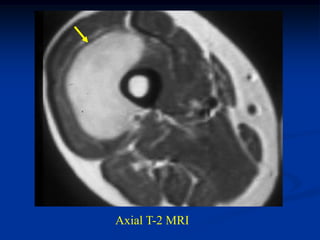

Case #259.2                   MFH with skip lesions

64 year male with painful soft tissue mass in thigh for 6 mos

Cor STIR   Ant STIR   Gad

Axial T-2   Lower T-2

Lower Gad

Sag Gad   Gad